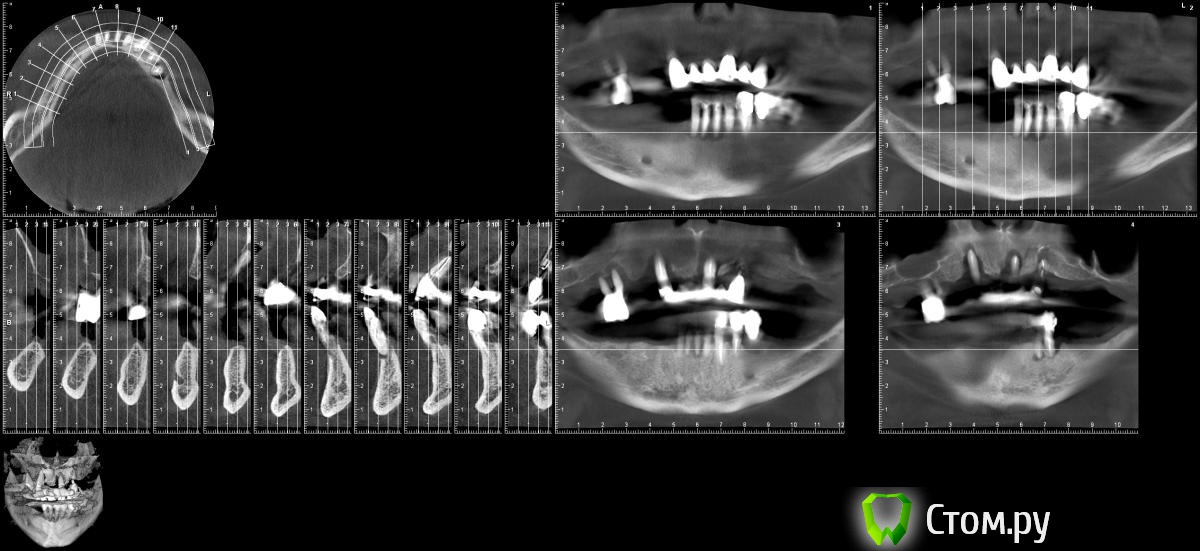

rezo47 Опубликовано 2 июля, 2014 Поделиться Опубликовано 2 июля, 2014 Пациент 50 лет обратился в клинику с целью восстановления жевательной эффективности на в/ч и н/ч посредством дентальных имплантантов. Был отправлен на кт. и вот результат.Я себе вижу это так:удаление всех зубов с заполнением лунок остеотропным материалом;полные съемные нейлоновые протезы;через 3 месяца в/ч синуслифт и 6 имплантантов, н/ч 6 или 4 и опять полные съемные нейлоновые протезы;и через 3-4 месяца протезирование конструкцией на винтах.Поправте если что не так. Спасибо. Ссылка на комментарий